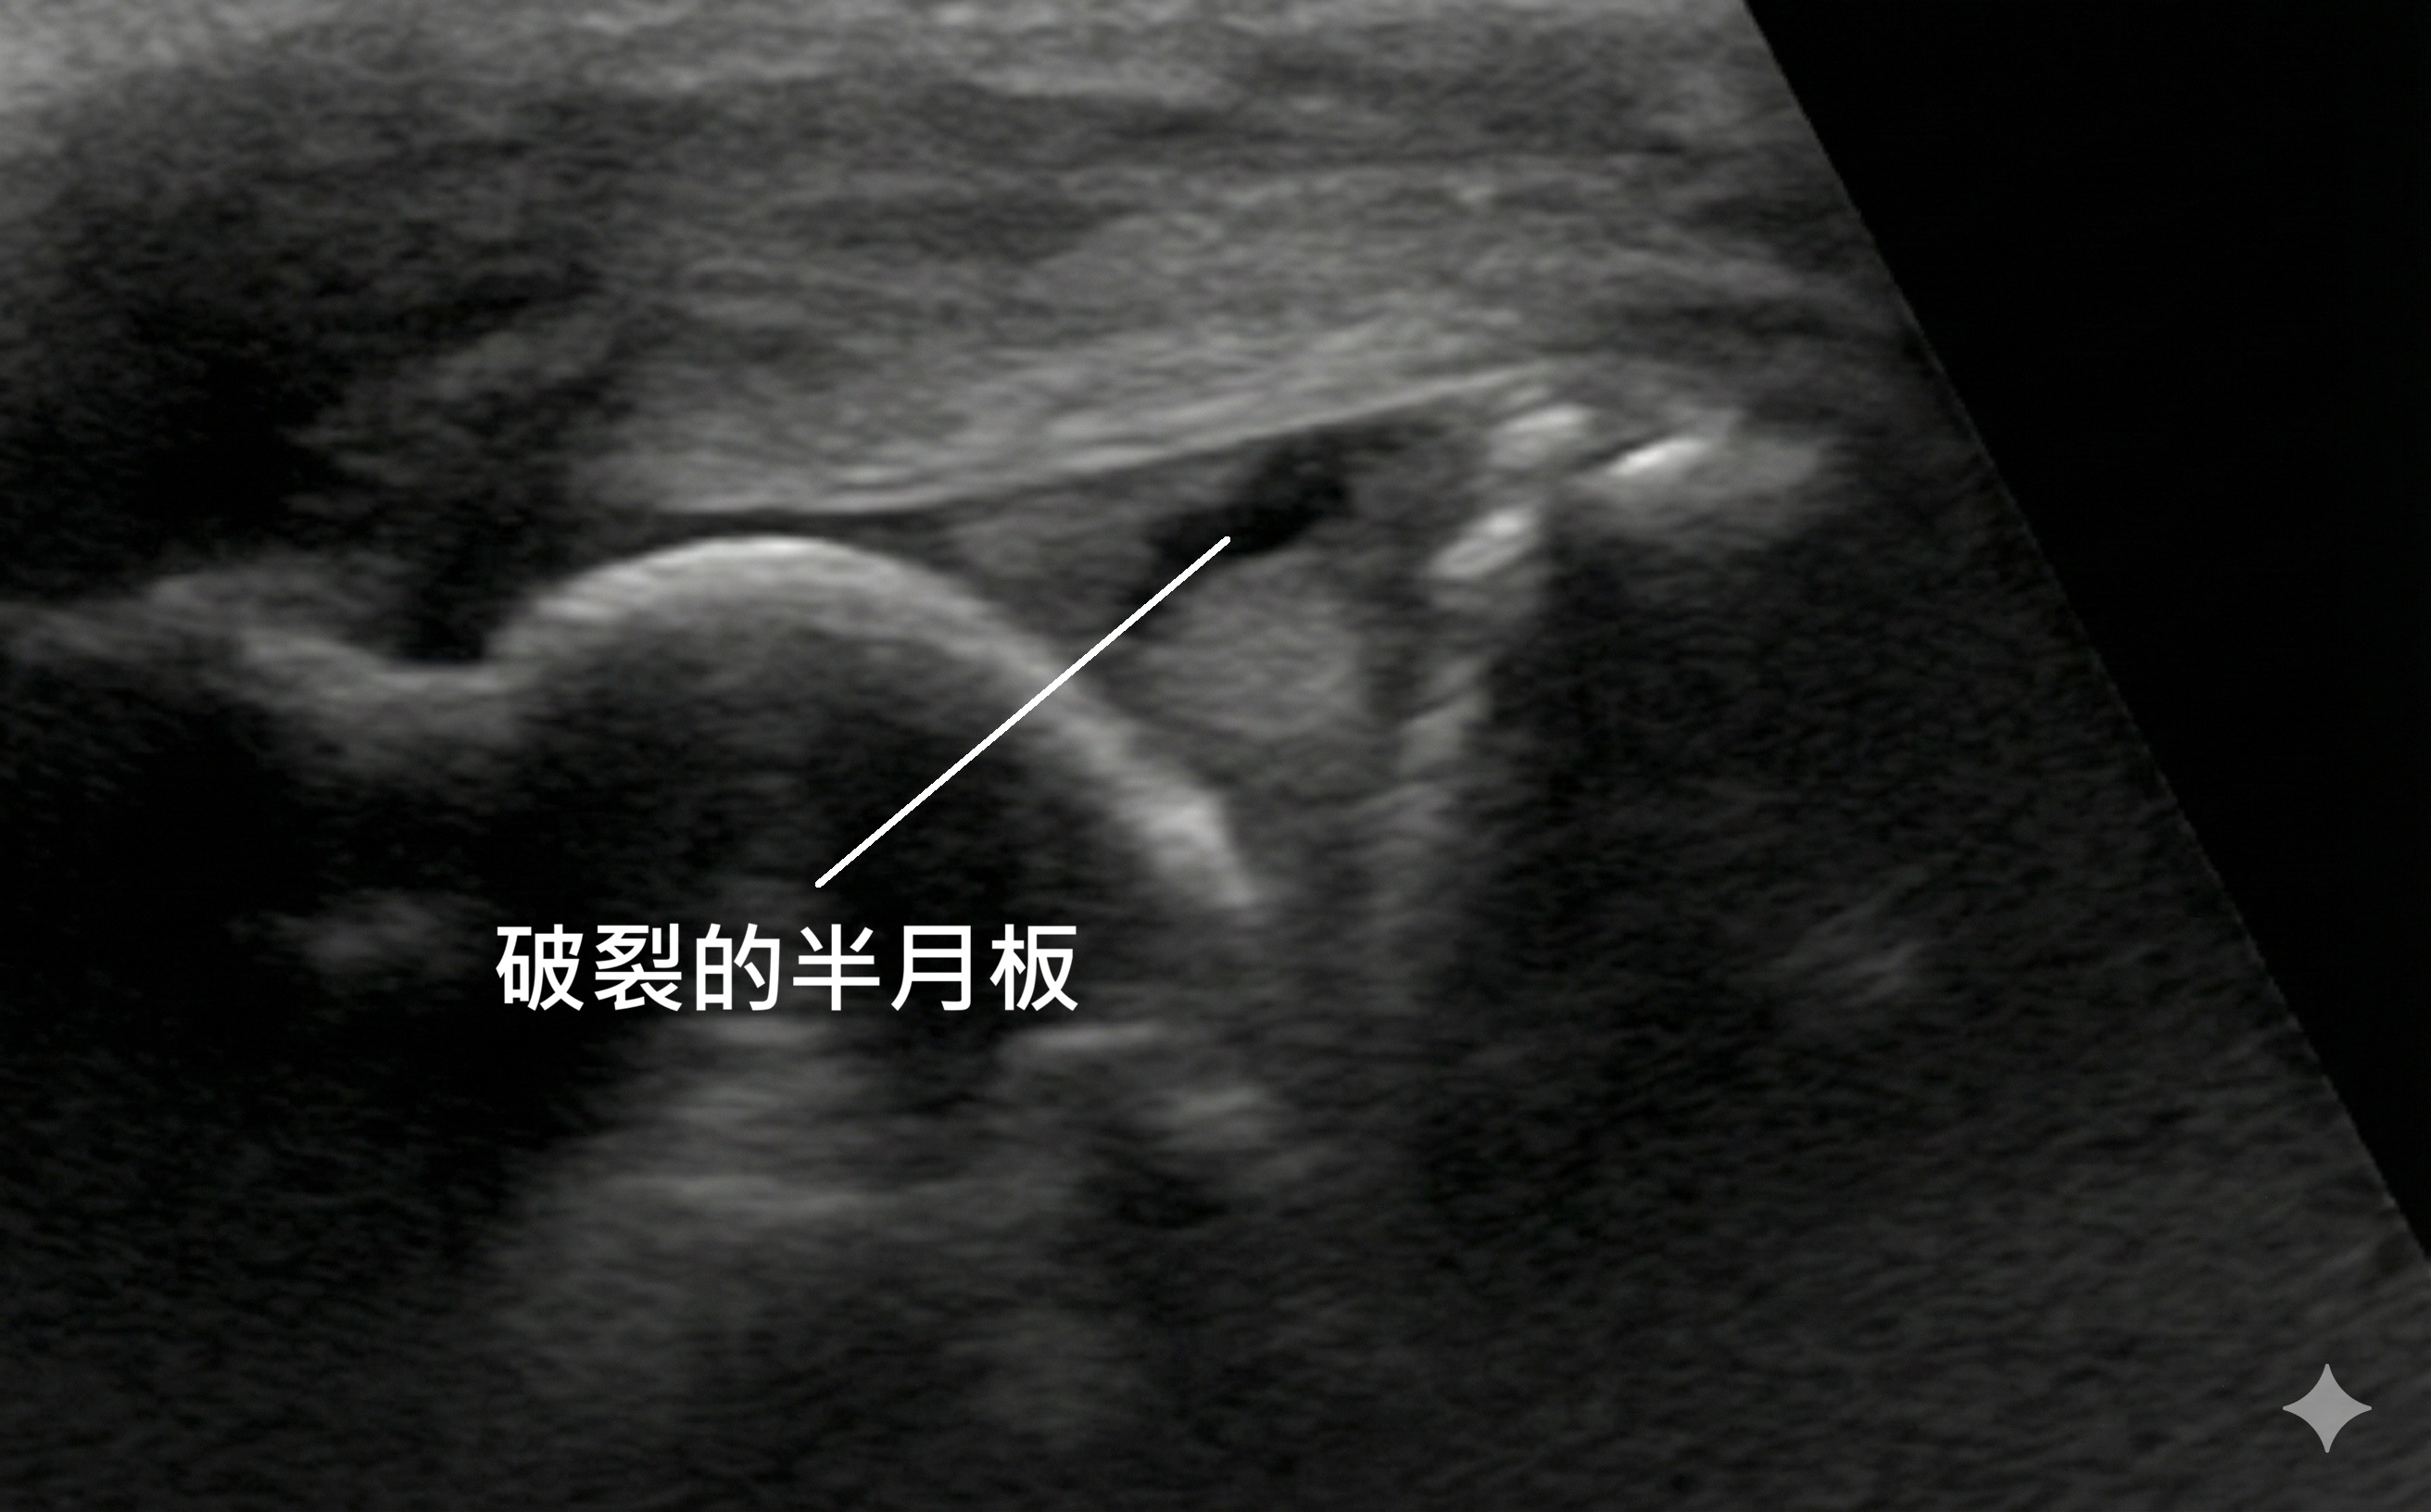

1. 高解析骨骼肌肉超音波 (第一線檢查)

在宸新復健科,我們使用高階超音波進行檢查,它有兩大優勢:

- 看積水: 半月板受傷常伴隨關節發炎積水。超音波能清楚看到關節囊被黑色的液體撐開,這是急性發炎的鐵證。

- 動態檢查: 這是超音波最強的地方。醫師會邊擠壓膝蓋、邊用探頭看,可以觀察到半月板是否不穩定地「被擠出來」(Meniscus Extrusion),或是看到明顯的撕裂裂縫。